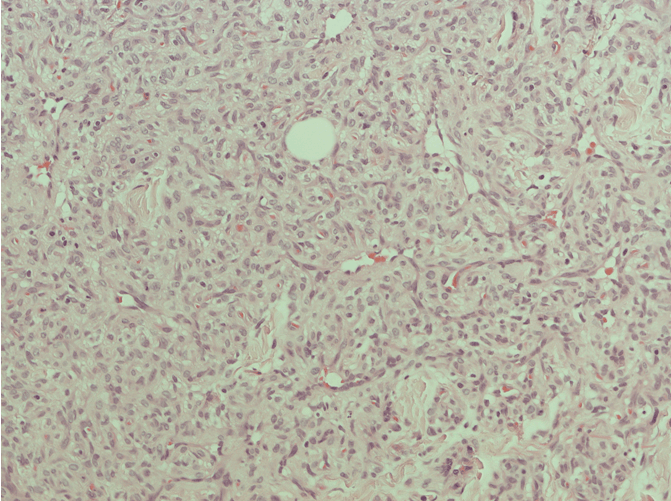

Histological examination of the specimen revealed oral mucous membrane, with underlying stroma showing a well-defined lesion (Figure 1). CD31 was positive, highlighting thin walled blood vessels. The lesion was positive for smooth muscle actin (Figure 2) and negative for S100. There was no atypia or malignancy, with features and immunostaining favoring a benign glomus tumor.

Figure 1: Hematoxylin and eosin stain (x100) tumor.